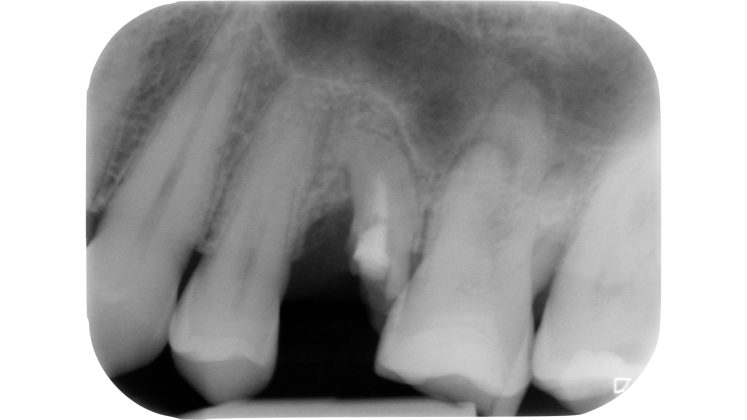

L’esecuzione di una corretta cavità d’accesso trae origine innanzitutto da una preliminare valutazione clinica e radiografica dell’elemento da trattare.

Devono essere valutate con molta attenzione la posizione dell’elemento in arcata e la sua inclinazione (Figure 6-7), l’entità e la posizione del processo carioso se presente, gli eventuali restauri posizionati sul dente e i rapporti con il parodonto: tutte queste considerazioni permetteranno al clinico di capire innanzitutto la mantenibilità e la possibilità di isolare mediante diga di gomma il dente. L’interpretazione degli esami radiografici consentirà inoltre di valutare alcuni parametri preoperatori di notevole importanza:

- qualità dei restauri posizionati sull’elemento dentale ed eventuali infiltrazioni secondarie;

- presenza di radiotrasparenze periradicolari o periapicali;

- difetti ossei di origine parodontale;

- aspetto della camera pulpare e del sistema canalare;

- anatomia radicolare e canalare;

- presenza di pregresse terapie canalari e valutazione della qualità delle stesse;

- presenza o sospetto di riassorbimenti interni o esterni;

- presenza o sospetto di perforazioni e fratture.

Un’attenta analisi di questi dati clinici e radiografici consentirà al clinico di ridurre notevolmente il rischio di errori grossolani in questa delicata fase del trattamento.